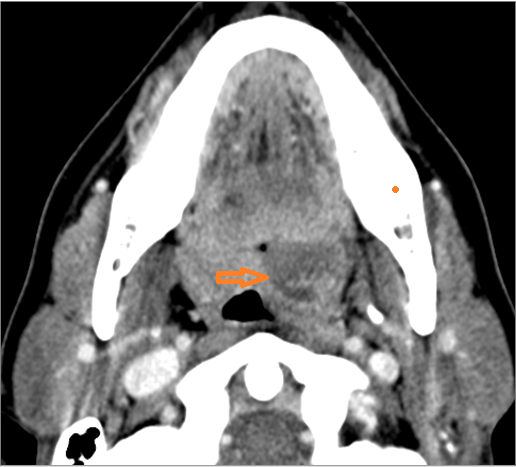

If there is suppurative retropharyngeal adenopathy what is the maximum short axis dimension of the largest suppurative node. MEASUREMENT